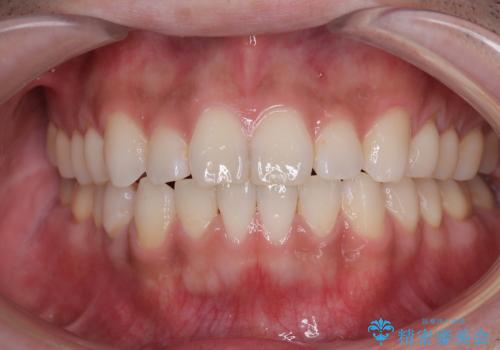

一年と数か月で矯正を終えることができました。

下顎前歯部には後戻り防止のワイヤーを装着しています。